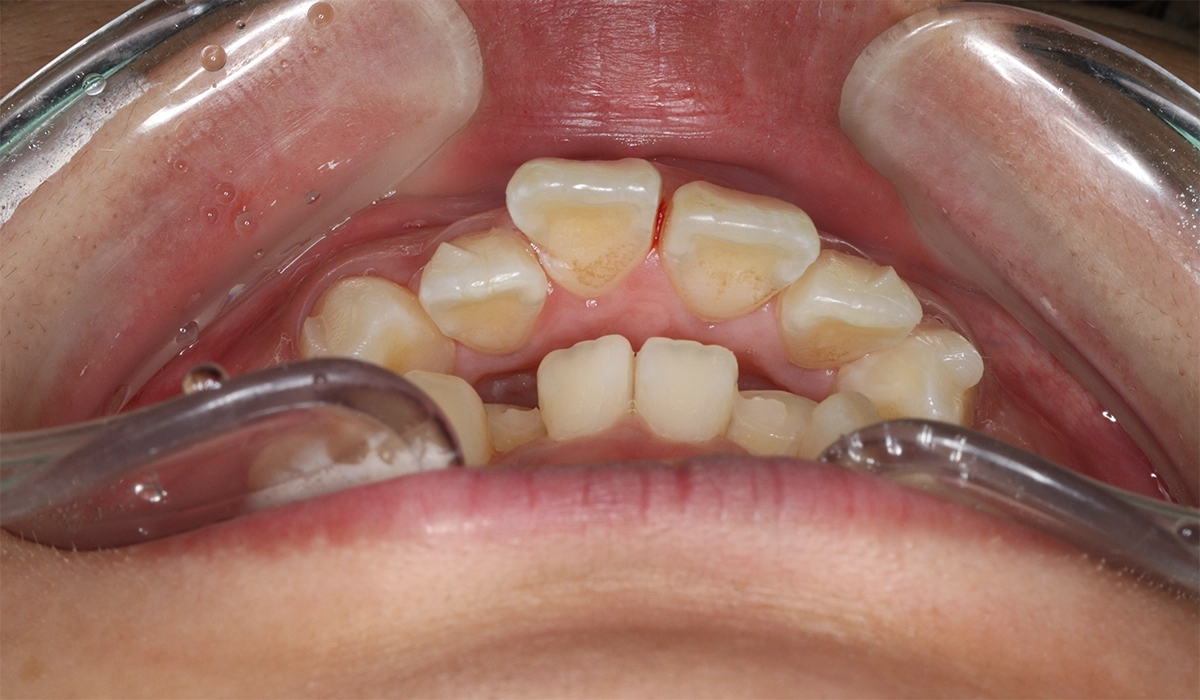

術前:前歯部あおり